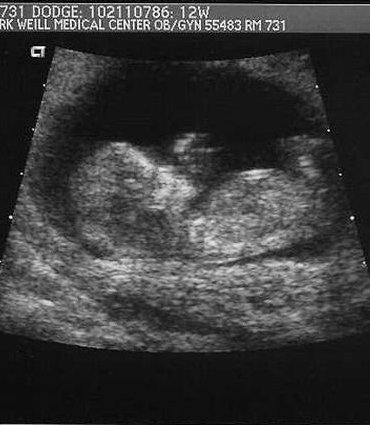

Jeff and I have some news...we're expecting a baby in

the spring, late March! Everything is going well. We

went for the first ultrasound a couple of weeks ago,

and that was pretty cool. The baby was very active

that day, moving around and waving. The parents are

all very excited. Of course, we're excited, too and a

little nervous.

good. I'll try to send over the ultrasound pictures

from a few weeks ago.